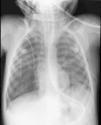

Caso 2Paciente de 10 días de vida que ingresa en la UCIP para control postoperatorio tras cirugía correctora de D-transposición de grandes arterias. Presenta quilotórax posquirúrgico, por lo que se procede a colocación de drenaje pleural derecho (Pneumocath® 8F). Durante la inserción, se produce traumatismo pericárdico con derrame pericárdico secundario y fractura accidental del catéter pleural, permaneciendo un fragmento en cavidad pleural (fig. 2). Se procede a retirada mediante toracotomía y a la colocación de nuevo catéter, sin incidencias.